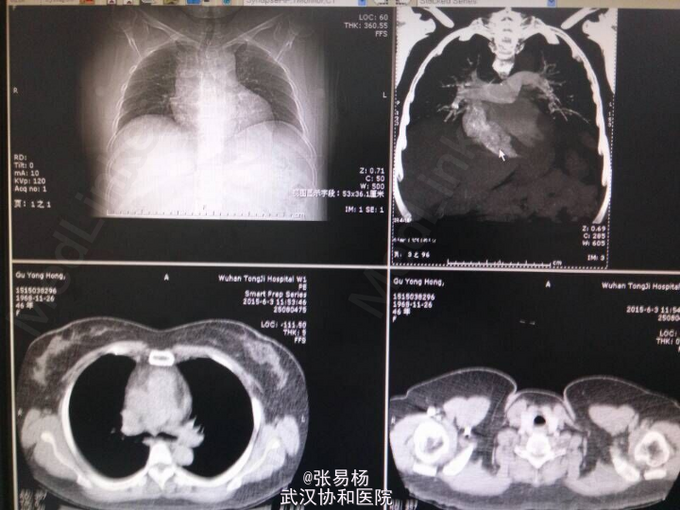

患者,女,47岁 主诉:双下肢胀痛不适10余天 现病史:患者于10余天前无明显诱因出现双下肢肿胀,有轻微压痛,久站及行走后加重,平卧后缓解,余无特殊症状。3天前门诊行双下肢彩超示:双侧小腿肌间静脉血栓形成。 既往有高血压病史3年余,口服利血平片,血压控制可余无特殊。

查体:双下肢水肿,指压征阳性,余无特殊。 辅检:肺动脉血管成像,CT-三维成像示:左肺动脉及其分支,右肺上叶肺动脉及其分支,右肺下叶后段肺动脉充盈缺损,考虑栓塞双肺血管纹理增强,考虑灌注不足所致。

行下腔静脉滤器植入术,术后予以抗凝,改善循环,预防感染等对症治疗